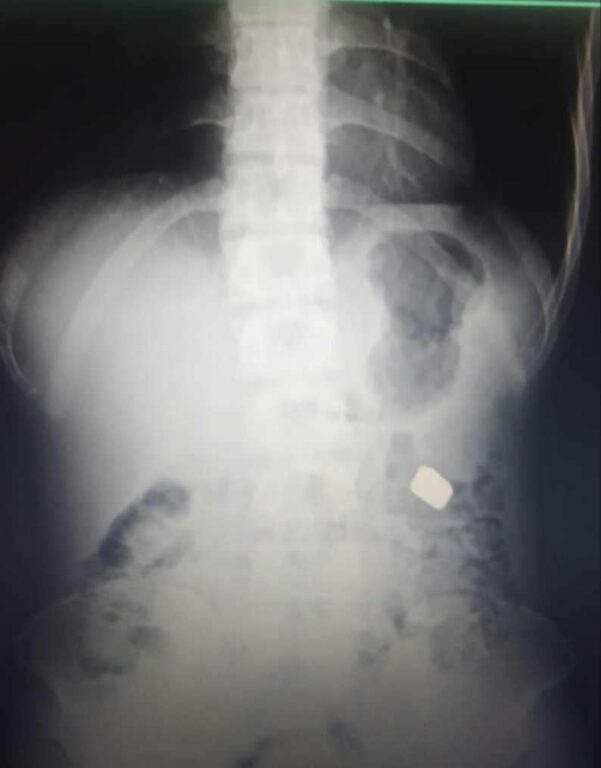

पीडितले आरोपित विरुद्ध चैत्र २९ गते जिल्ला प्रहरी कार्यालयमा उजुरी दिएकी थिईन् । आरोपितको अनुसन्धान गर्ने क्रममा उनको साथवाट १५ हजार नगद समेत बरामत गरिएको जिल्ला प्रहरी कार्यालयका प्रहरी निरीक्षक सुमित कुस्वाहाले बताए । आरोपितले चोरी गरेको सुन निलेको आशंकामा एक्स–रे गर्दा धातु जस्तो पदार्थ देखिएको र विविध विधिवाट सुन निकालिएको प्रहरी निरीक्षक कुस्वाहाले जानकारी दिए ।